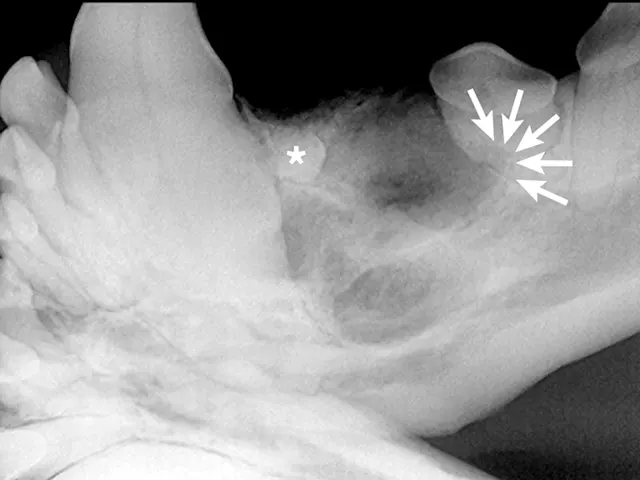

Full-mouth radiographs were obtained, with particular attention on the clinically missing mandibular premolars and the areas affected by gingival masses. Radiographs revealed unerupted mandibular 1st premolars situated in apparent cystic lesions, expansion of which resulted in involvement of the mandibular canines and 2nd premolar teeth. The apical portion of the mesial root of the mandibular premolar (306) was partially resorbed. Maxillary premolars were rotated bilaterally, but there were no periodontal consequences. Incidental findings included a supernumerary maxillary left first premolar 1 (205) and fusion of the roots of the left and right mandibular premolar 2 teeth (306 and 406). Horizontal alveolar bone loss was present at the area of 206, with radiolucency of the furcation area of 206 (Figures 3-6); the buccal aspect of 206 was covered by the gingival mass. Probing of the furcation was possible only from the palatal side and did not reveal furcation involvement.

FIGURE 2

Oral examination revealed nonvisible mandibular first premolars (stars), mandibular mucosal trauma by the maxillary incisors (arrows), and trauma to the left mandibular canine tooth (304) by the left second maxillary incisor (202; circle).